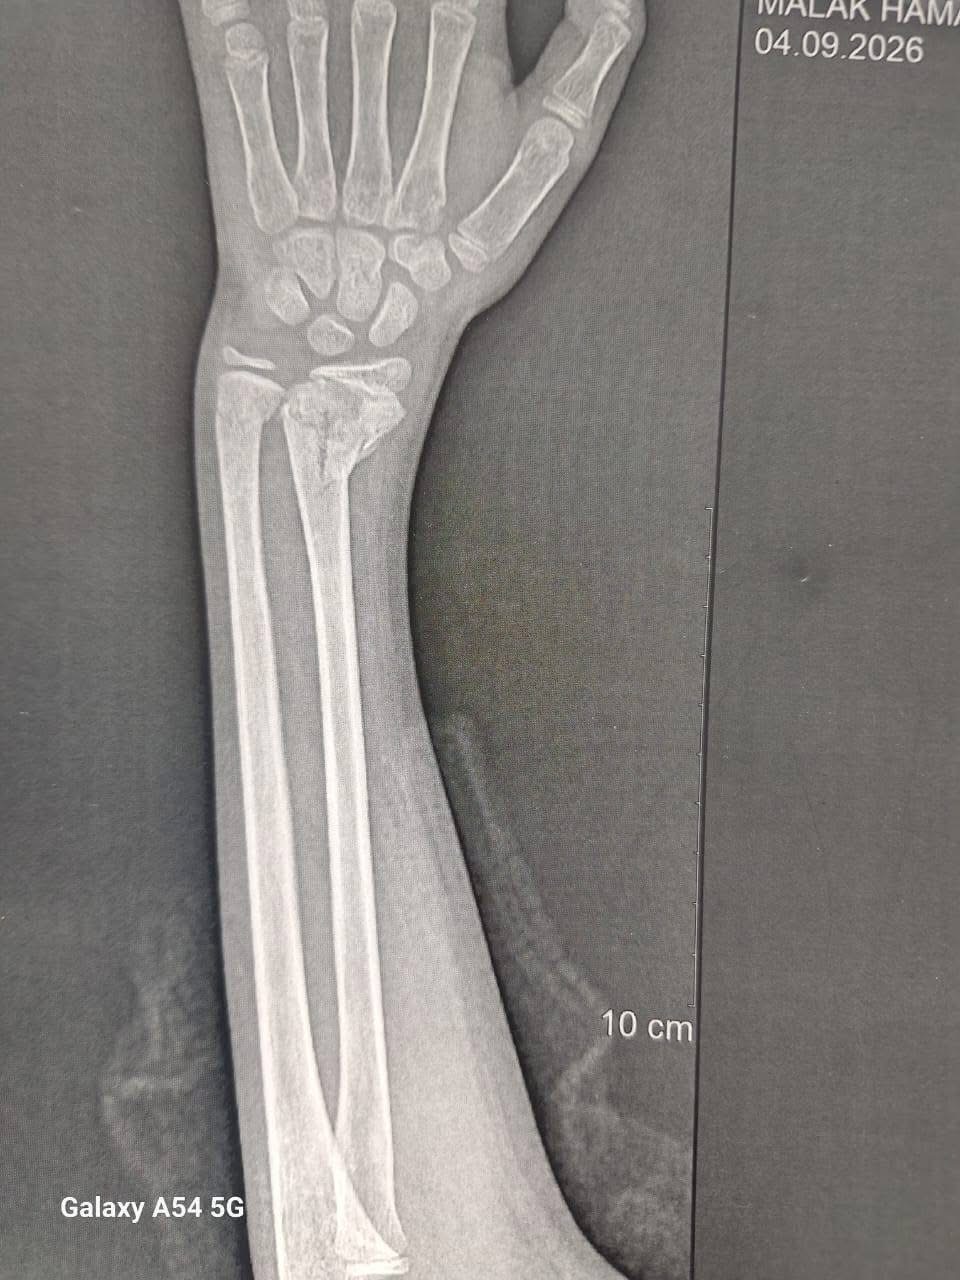

وأضاف الخضيري، أنه تم إجراء 3 عمليات بقسم الأنف والأذن، و3 عمليات بقسم العظام، بالإضافة إلى 4 عمليات جراحية متنوعة، بما يعكس جاهزية الأقسام المختلفة بالمستشفى لتقديم خدمات طبية متكاملة للمرضى